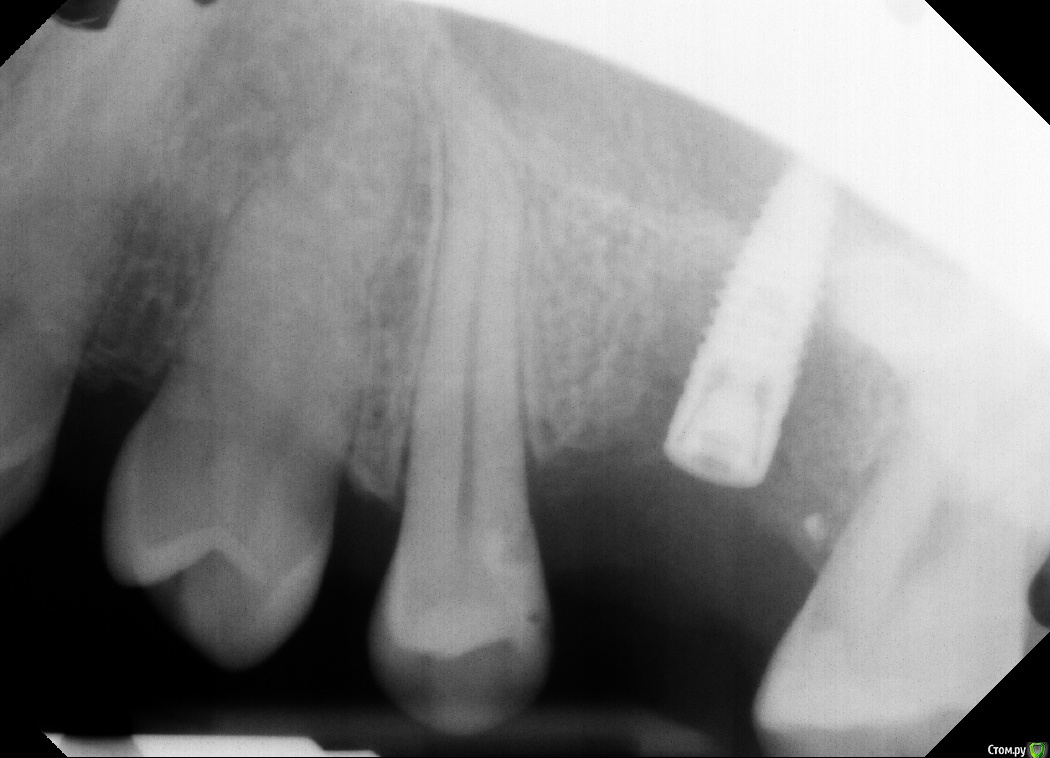

AlinaKh Опубликовано 20 декабря, 2016 Автор Поделиться Опубликовано 20 декабря, 2016 Чтоб ответить на этот вопрос надо знать изначальную ситуацию, ваш анамнез и ход той операции. Для начала.Всем спасибо! Имплант был удалён, вот снимки до и после Ссылка на комментарий

IvanK Опубликовано 21 декабря, 2016 Поделиться Опубликовано 21 декабря, 2016 да, удален полностью) 1 Ссылка на комментарий